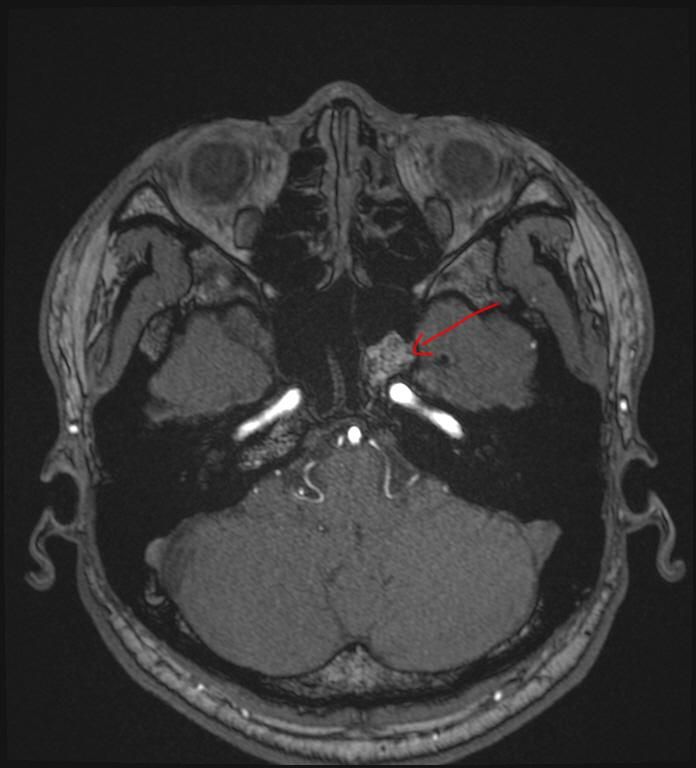

mri 사진을 봤을 때 정확히 어디가 막힌 걸까요? 그리고 치료는 할 수 있는 걸까요???

• 1번 째 사진

올려주신 영상 관련 보다 더 자세한 분석 원하시면 영상의학과 전문의한테 물어보셔야 해요

말씀하신 증상 관련 답변 드리자면 15년동안 지속된 귀와 코 사이 막힘 증상은 이관(유스타키오관) 기능 장애일 가능성이 높습니다. 진한 콧물을 강하게 들이마신 후부터 증상이 생겼다면, 이관이 분비물이나 압력 변화로 막히거나 손상되었을 가능성이 있습니다. 이관은 코 뒤쪽과 귀 중이를 연결하는 통로로, 막히면 귀먹먹함, 압력감, 울림 증상 등이 지속될 수 있습니다. MRI나 CT를 통해 이관 주변 구조(비인두, 부비동, 중이강 등)의 해부학적 이상을 더 정확히 확인해야 합니다.